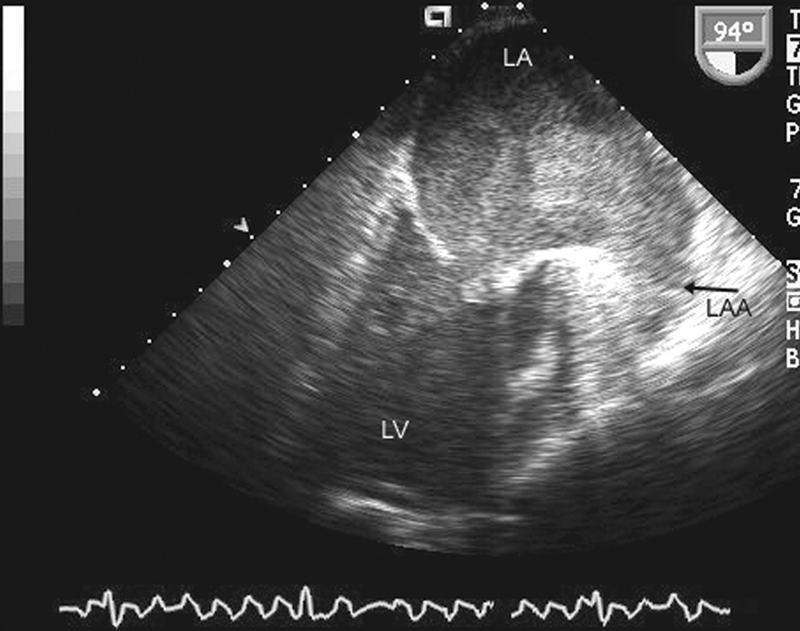

فحوصات تشخيصية لبعض امراض القلب والشرايين التاجية